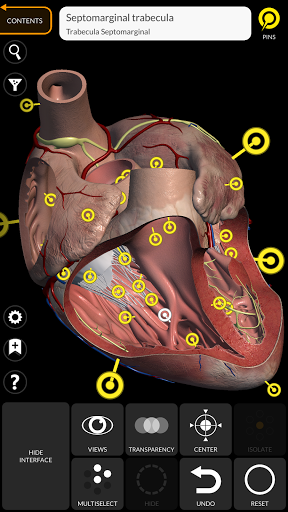

"Anatomy 3D Atlas" cho phép bạn nghiên cứu giải phẫu người theo cách dễ dàng và tương tác.

Thông qua giao diện đơn giản và trực quan, bạn có thể quan sát mọi cấu trúc giải phẫu từ mọi góc độ.

Các mô hình giải phẫu 3D đặc biệt chi tiết và có kết cấu lên đến độ phân giải 4k.

Việc phân chia theo vùng và chế độ xem được xác định trước giúp quan sát và nghiên cứu các bộ phận hoặc nhóm hệ thống riêng lẻ và mối quan hệ giữa các cơ quan khác nhau.

• Hệ thống tim mạch

• Chức năng đánh dấu để lưu chế độ xem tùy chỉnh

• Bằng cách chọn một mô hình hoặc một ghim, thuật ngữ giải phẫu liên quan sẽ hiển thị

• Các thuật ngữ giải phẫu có thể được hiển thị bằng hai ngôn ngữ cùng lúc